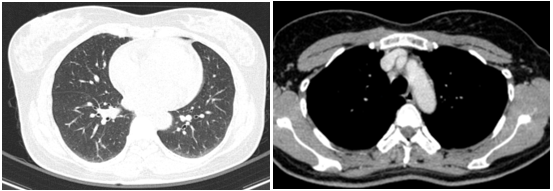

Cắt lớp vi tính lồng ngực:

Hình 2: Hình ảnh cắt lớp vi tính lồng ngực chưa phát hiện bất thường

Cắt lớp vi tính ổ bụng:

Hình 3: Hình ảnh cắt lớp vi tính ổ bụng chưa phát hiện bất thường